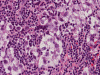

Pathology of the Case: The sample submitted for frozen section has a papillary structure which can be identified as the choroid plexus (Panel C). The center of the choroid plexus is expanded by some large cells accompanied by some smaller cells presumably lymphocytes (Panel D and E). On hematoxylin and eosin stain of the permanent sections, the tumor is composed of clusters of large cells in a background of lymphocytes. On higher magnification, the large cells have enlarged nuclei with prominent nucleoli. No trophoblasts or nor seminomatous component are identified. Immunohistochemistry demonstrated strong positive reactivity for placental alkaline phosphatase (PLAP) (Panel I) and CD117 (c-kit) in the large atypical cells (Panel J). The lymphocytes in the background are strongly immunoreactive for leukocyte common antigen (LCA) (Panel K) but negative for PLAP and CD117.

The discussion here will be limited predominantly to germinoma. Histologically, germinoma has very characteristic features heralded by large, atypical germinoma cells in a background of benign lymphocytes. The germinoma cells are usually huge, with a moderated amount of cytoplasm, and with prominent nucleoli. These cells, even though large, are rarely bizarre. The proportion of germinoma cells with lymphocytes can be highly variable. While most cases show a good mix of both component, the small biopsies yielded by endoscopic biopsy can sample in areas that are lymphocyte predominant or germinoma cell predominant areas which lead to diagnostic pitfalls. It should also be reminded that germinoma has a strong tendency to undergo granulomatous changes. Such granulomatous changes may completely efface the usually big cell-small lymphocyte classic pattern. These biopsies, however, would histologically suggest infection but the clinical history usually would not. Knowing the clinical history is often helpful. Trophoblastic cells could be seen and their presence may indicate a worse prognosis for germinomas. Non-seminomatous component such as embryonal cell carcinoma, yolk sac tumor (endodermal sinus tumor), and choriocarcinoma should also be identified if present.